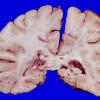

MYELIN (NON-IMMUNE MEDIATED)

Fat Embolism (9)